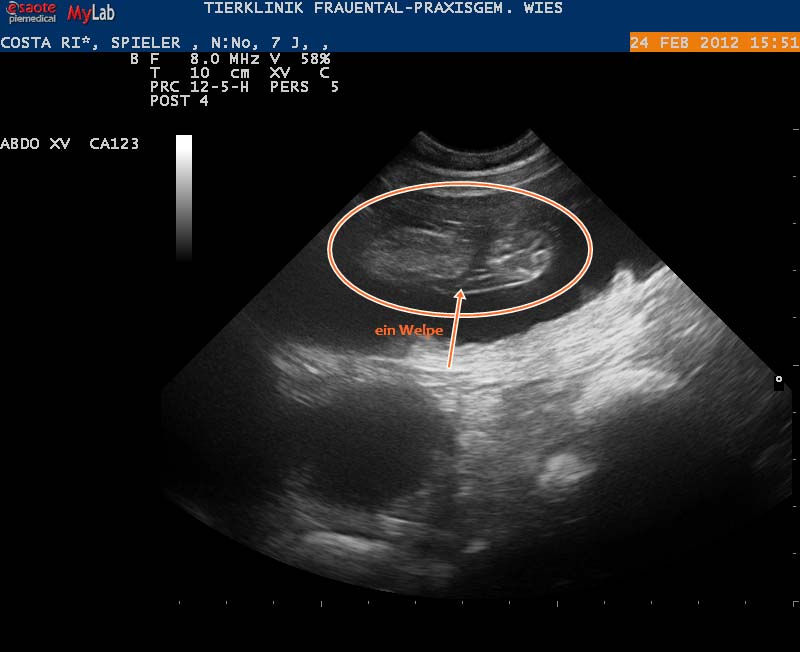

13.02.2012: Ultraschalltermin

Das Date der beiden am 20.1. hat Folgen. Der Tierarzt hat uns die Trächtigkeit von Costa-Rica bestätigt und wir freuen uns schon sehr auf den Nachwuchs.

Links: Eine Fruchtblase am 25. Trächtigkeitstag - Rechts: Ein Welpe 10 Tage später